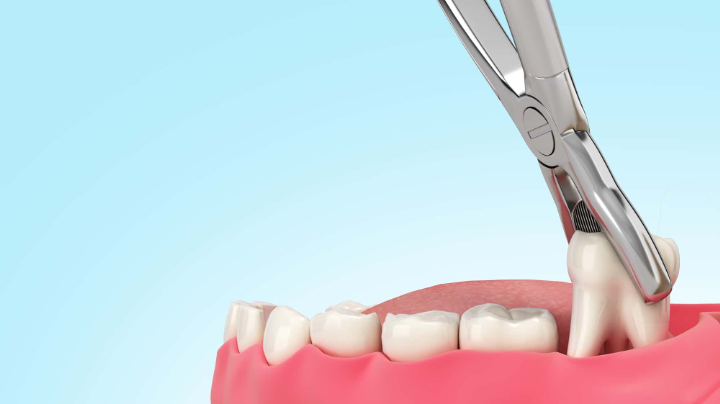

真っ直ぐに生えている場合

まっすぐに生えている親知らずの抜歯は、他の歯と同様に行われます。局所麻酔をして痛みを感じないようにしてから、器具を使用して脱臼させて抜き取ります。

処置後は痛み止めや抗生剤が処方されるので、歯科医師の指示に従って使用しましょう。腫れや痛みが出ることもありますが、2〜3日をピークに1週間程度で軽減していきます。